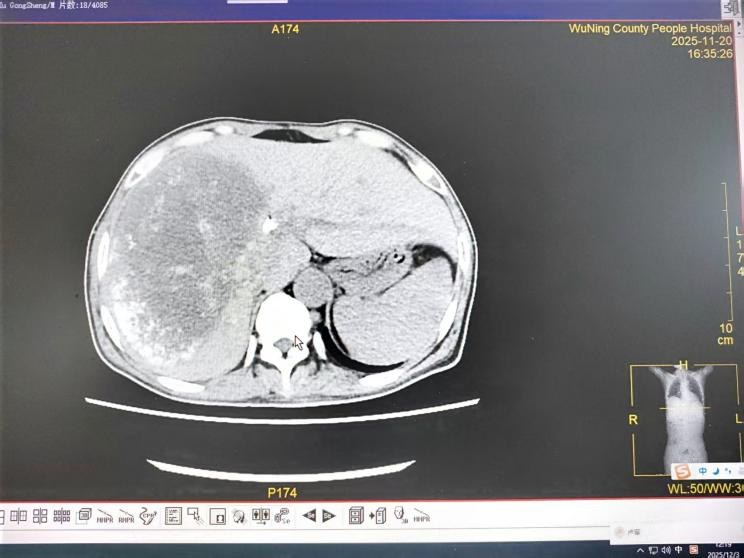

对于已失去手术机会的晚期肝癌伴梗阻性黄疸患者,肿瘤科介入团队发挥了关键作用。一例直肠癌肝、肾上腺多发转移导致严重黄疸、肝功能受损的患者,情况危急。团队首先行“经皮胆管支架植入+引流术”,快速解除胆道梗阻,改善肝功能。待患者状况稳定后,又为其制定了序贯的“肝动脉灌注化疗联合栓塞术(HAIC+TACE)”方案。经过数次介入治疗,患者肝内转移灶明显缩小,黄疸完全消退,肿瘤标志物显著下降,生活质量得到极大改善。这凸显了我院在晚期肿瘤并发症处理及局部介入综合治疗方面的强大技术支撑。

2025年11月20日CT示: